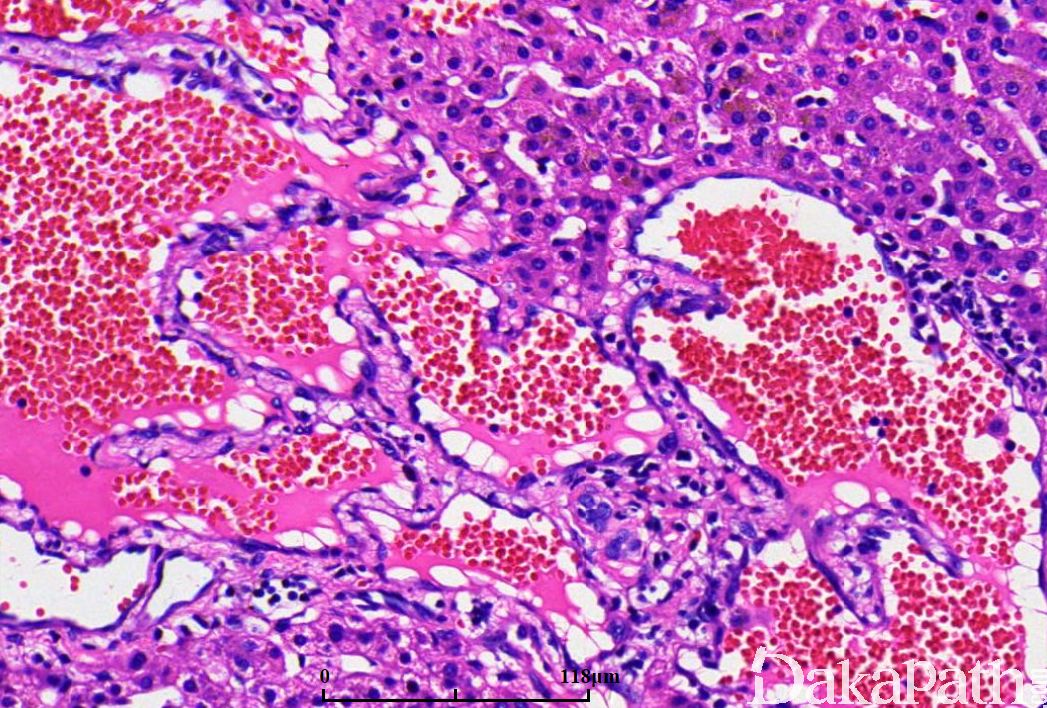

典型的海绵状血管瘤由大小不等的血管腔组成,管腔充满血液,内衬单层扁平内皮细胞;

血管间可见厚度不一的纤维分隔;纤维间质中可见树枝状小血管;

部分病例边缘区可见扩张的血管腔伸入周围肝实质中;